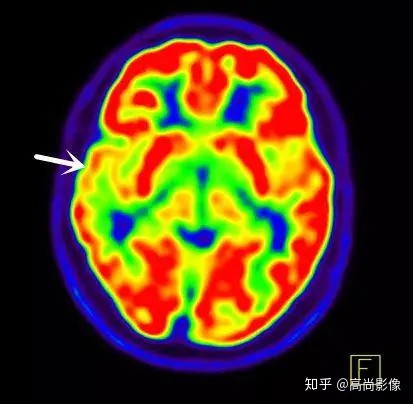

這種情況(轉(zhuǎn)移瘤尋找原發(fā)灶的患者)有很強的PET/CT檢查指征,在骨科醫(yī)生的建議下,方大爺很快預(yù)約了全身18F-FDG代謝顯像,第二天順利完成了檢查。

(胸椎骨轉(zhuǎn)移合并病理性骨折)

(右側(cè)髖臼骨轉(zhuǎn)移)

(右肺癌全身多發(fā)轉(zhuǎn)移)

(右肺上葉中央型肺癌)

方大爺?shù)腜ET/CT結(jié)果強烈提示肺癌伴全身多發(fā)轉(zhuǎn)移,已經(jīng)失去手術(shù)機(jī)會,但仍有繼續(xù)化療的機(jī)會。